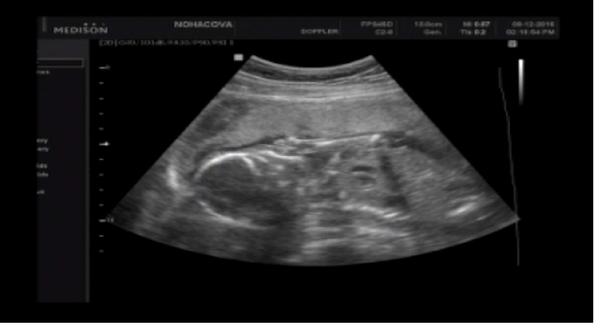

Ahoj maminky a budoucí maminky 😉 Prosím, poradila byste mi některá, co vidíte na fotce z ultrazvuku ve 20. týdnu za pohlaví? Určitě jste foteček viděly už mraky, proto vás žádám o radu...Nechci nikoho ovlivnit, proto svůj tip řeknu později 🙂 Děkuju moc!!!

Hlásím,že máme potvrzeného Vojtíška a je to prý pořádný bobíšek 🙂 hlavně,že se má v bříšku dobře 🙂